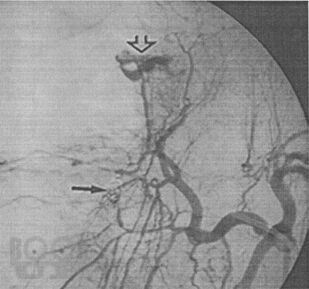

В пособии с современных позиций рассматриваются вопросы клинической и инструментальной диагностики травм печени и диагностическая ценность каждого из них. Сформулированы хирургическая тактика при травмах печени и критерии определяющие хирургическую тактику.